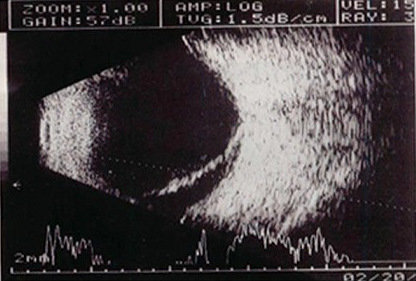

12、单项选择题

男性,70岁,左下肢橡皮肿,阴囊肿大如橄榄球大小,阴囊壁增厚,B超声像图如下,患者有可能是下列哪个疾病()